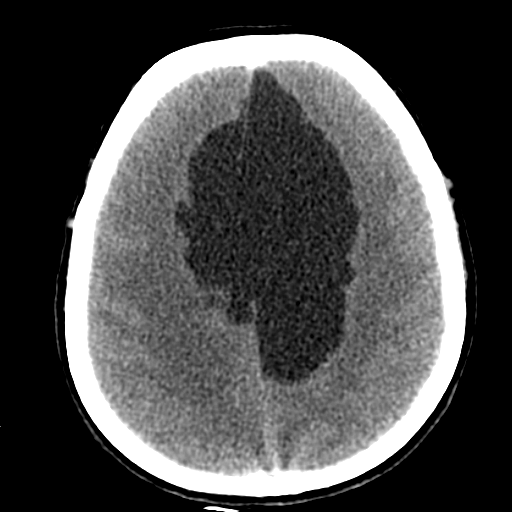

Больному около 55 лет, клинику дает не сколько само образование, а компрессия структур мозга, базально вообще беда (отчасти видно компреммию некоторых базальных цистерн мозга). Сразу скажу насчет эпидермоидной кисты - ДВИ не будет :)

Однозначно киста, значит, осталось выяснить какая, холестеатома или арахноидальная?

Эпидермоид может расти, при ТИА может быть случайной находкой. А тут ещё окклюзионная гидроцефалия.

Может, это две межполушарные арахноидальные кисты?

На объем как то тоже не похоже. , сигнал равномерный и такой же как и от ликвора. Если расценивать как последствия ОНМК так это как должно было " рвануть" да еще и с поражением желудочков - не пациент бы вряд ли выжел. Как же сложно в этом к/т ! Не знаю может это глупо, но у меня пока впечатление о врожденной патологии мозга. А с контрастом не делали ? Или вам и так все понятно, Сергей Николаевич , тогда поделитесь мыслями пожалуйста.

Создается впечатление о нехватке/недостатке мозгового вещества.